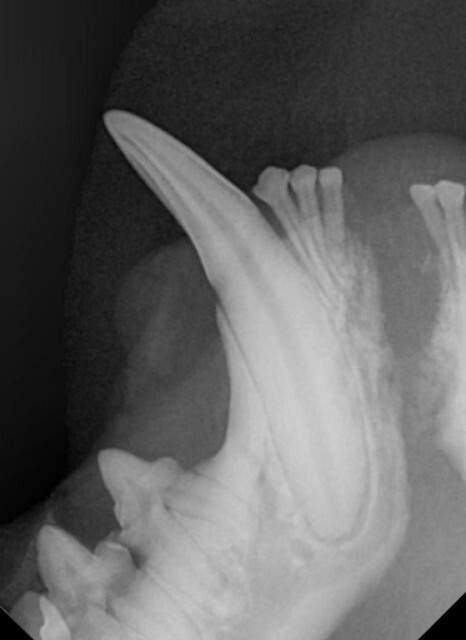

육안 검사상 얼굴 쪽에 아주 강한 충격을 받은 것으로

의심되는 상황이었습니다.

왼쪽 위 송곳니 깨짐과 아래턱뼈가 분리되어 있고

왼쪽 안구가 탈출되어 있는 안 좋은 상황이었습니다.

체력을 회복한 후 분리된 아래턱뼈를 결합하는

수술을 진행하였으나 분리된 채로 방치된 시간 동안

우측 턱뼈가 중앙으로 이동하여 위 어금니와 교합이

맞지 않는 상태였습니다.

아래턱뼈를 다시 정상 위치로 이동시키기 위한

교정 치료도 함께 진행되었습니다.